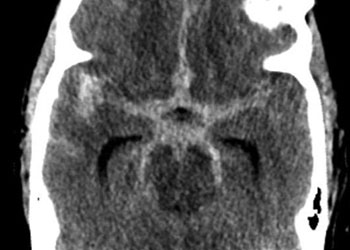

Brain:

Cerebellar Hemangioblastoma

Author: Michael Brisman M.D., F.A.C.S., Read More!